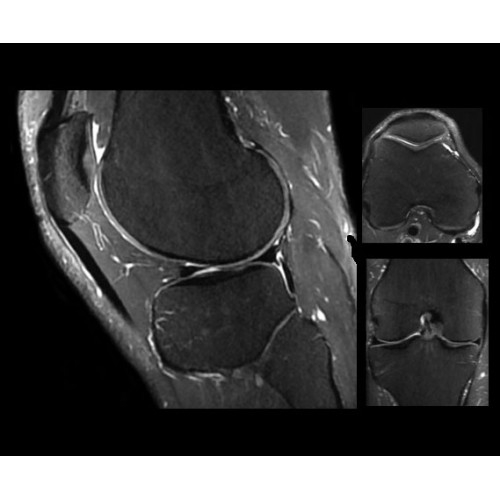

SIGNA PET/MR 3.0T — это гибридная система, в которой совмещаются две принципиально разные технологии — магнитно-резонансную томографию (МРТ) и позитронно-эмиссионную томографию (ПЭТ). Система отличающийся высокой чувствительностью и эффективностью и предназначена для диагностики в области онкологии, неврологии, кардио-васкулярных исследований, исследований воспалительных процессов.

Компания GE Healthcare представляет революционную, полностью интегрированную систему SIGNA PET/MR1, в которой сочетаются времяпролетная технология (TOF) и возможности напряженности магнитного поля 3.0 Тл. Мы поможем вам поднять исследования на более высокий уровень. SIGNA PET/MR позволяет достичь впечатляющей точности и скорости исследований, а благодаря новейшей технологии реконструкции Q.Clear2 качество изображений улучшается в два раза. Кроме того, в систему включен полный набор клинических приложений и гибких катушек для проведения любых видов исследования, открывая для вас возможности визуализации, о которых вы даже не догадывались.

В систему SIGNA PET/MR встроены запатентованные детекторы кремниевого фотоумножителя (SiPM) и сверхчувствительные кристаллические сцинтилляторы на основе лютеция толщиной 25 мм. Благодаря этому обеспечивается исключительная чувствительность и возможность использования времяпролетной диагностики (TOF).

Кроме того, в результате использования технологии TOF и инновационной технологии реконструкции Q.Clear вы сможете добиться прекрасного соотношения сигнал/шум. А благодаря технологии нулевого времени эхо (ZTE) визуализировать костную структуру без ионизирующего излучения. Все эти разработки для улучшения качества сканирования и точности анализа помогут вам использовать весь потенциал ПЭТ/МРТ.

Впечатляющие клинические возможности

Система SIGNA PET/MR предлагает впечатляющие клинические возможности и открывает доступ к наиболее полным пакетам программных приложений.

• TurboTOF — инновационная технология позволяет корректировать коэффициент затухания сигнала и минимизировать потери анатомических данных, создавая МР-систему для количественной визуализации.

• Q.Clear — в основу технологии легли накопленные знания о том, как минимизировать помехи при реконструкции и получить четкое изображение. При значительном улучшении качества изображения сохраняется точность расчетов. Сочетание технологии TOF и реконструкции Q.Clear — ваш надежный помощник для получения точных и достоверных данных.

• МРТ с функцией нулевого времени эхо (ZTE) отличается точностью, возможностью персональных настроек и отсутствием ионизирующего излучения. Она приходит на смену традиционному исследованию на основе рентгеновского излучения. МРТ с функцией нулевого времени эхо (ZTE) на базе SIGNA ПЭТ/МРТ является более надежной и быстрой по сравнению с системами, использующими сверхмалое время эхо (UTE).